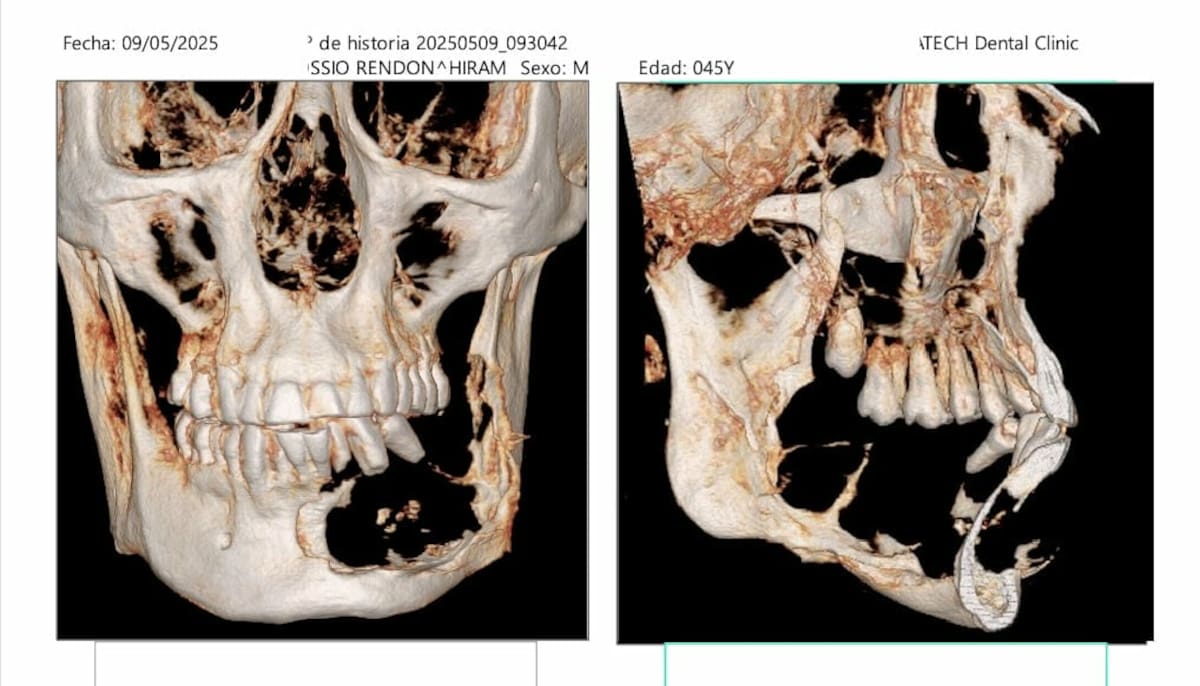

HERMOSILLO, Sonora. — Hiram Kossio fue diagnosticado hace dos años con un ameloblastoma en la zona maxilar inferior, lo que pone en riesgo su calidad de vida al prácticamente deshacer parte de los huesos de su rostro y mandíbula.

El ameloblastoma es un tumor propio de la zona del maxilar; puede ser superior o inferior, pero en el caso de Kossio creció en la parte inferior derecha de su mandíbula.

Esto ha provocado que algunos de sus dientes se muevan, al no tener el soporte del hueso mandibular en esa área, además de que continuamente retiene líquidos, lo que le produce una hinchazón extrema e incomodidad.

La cirugía, explicó Kossio, se llama resección mandibular y consiste en cortar la zona afectada por el tumor para después sustituirla.

En mi caso, mientras la doctora trabaje en extirpar el tumor y la mandíbula, un ortopedista va a estar haciendo el corte en una zona de la pierna —no recuerdo si es el fémur o la cadera—, y después un cirujano microvascular le va a dar la forma a ese hueso para colocarlo en la mandíbula”, detalló.